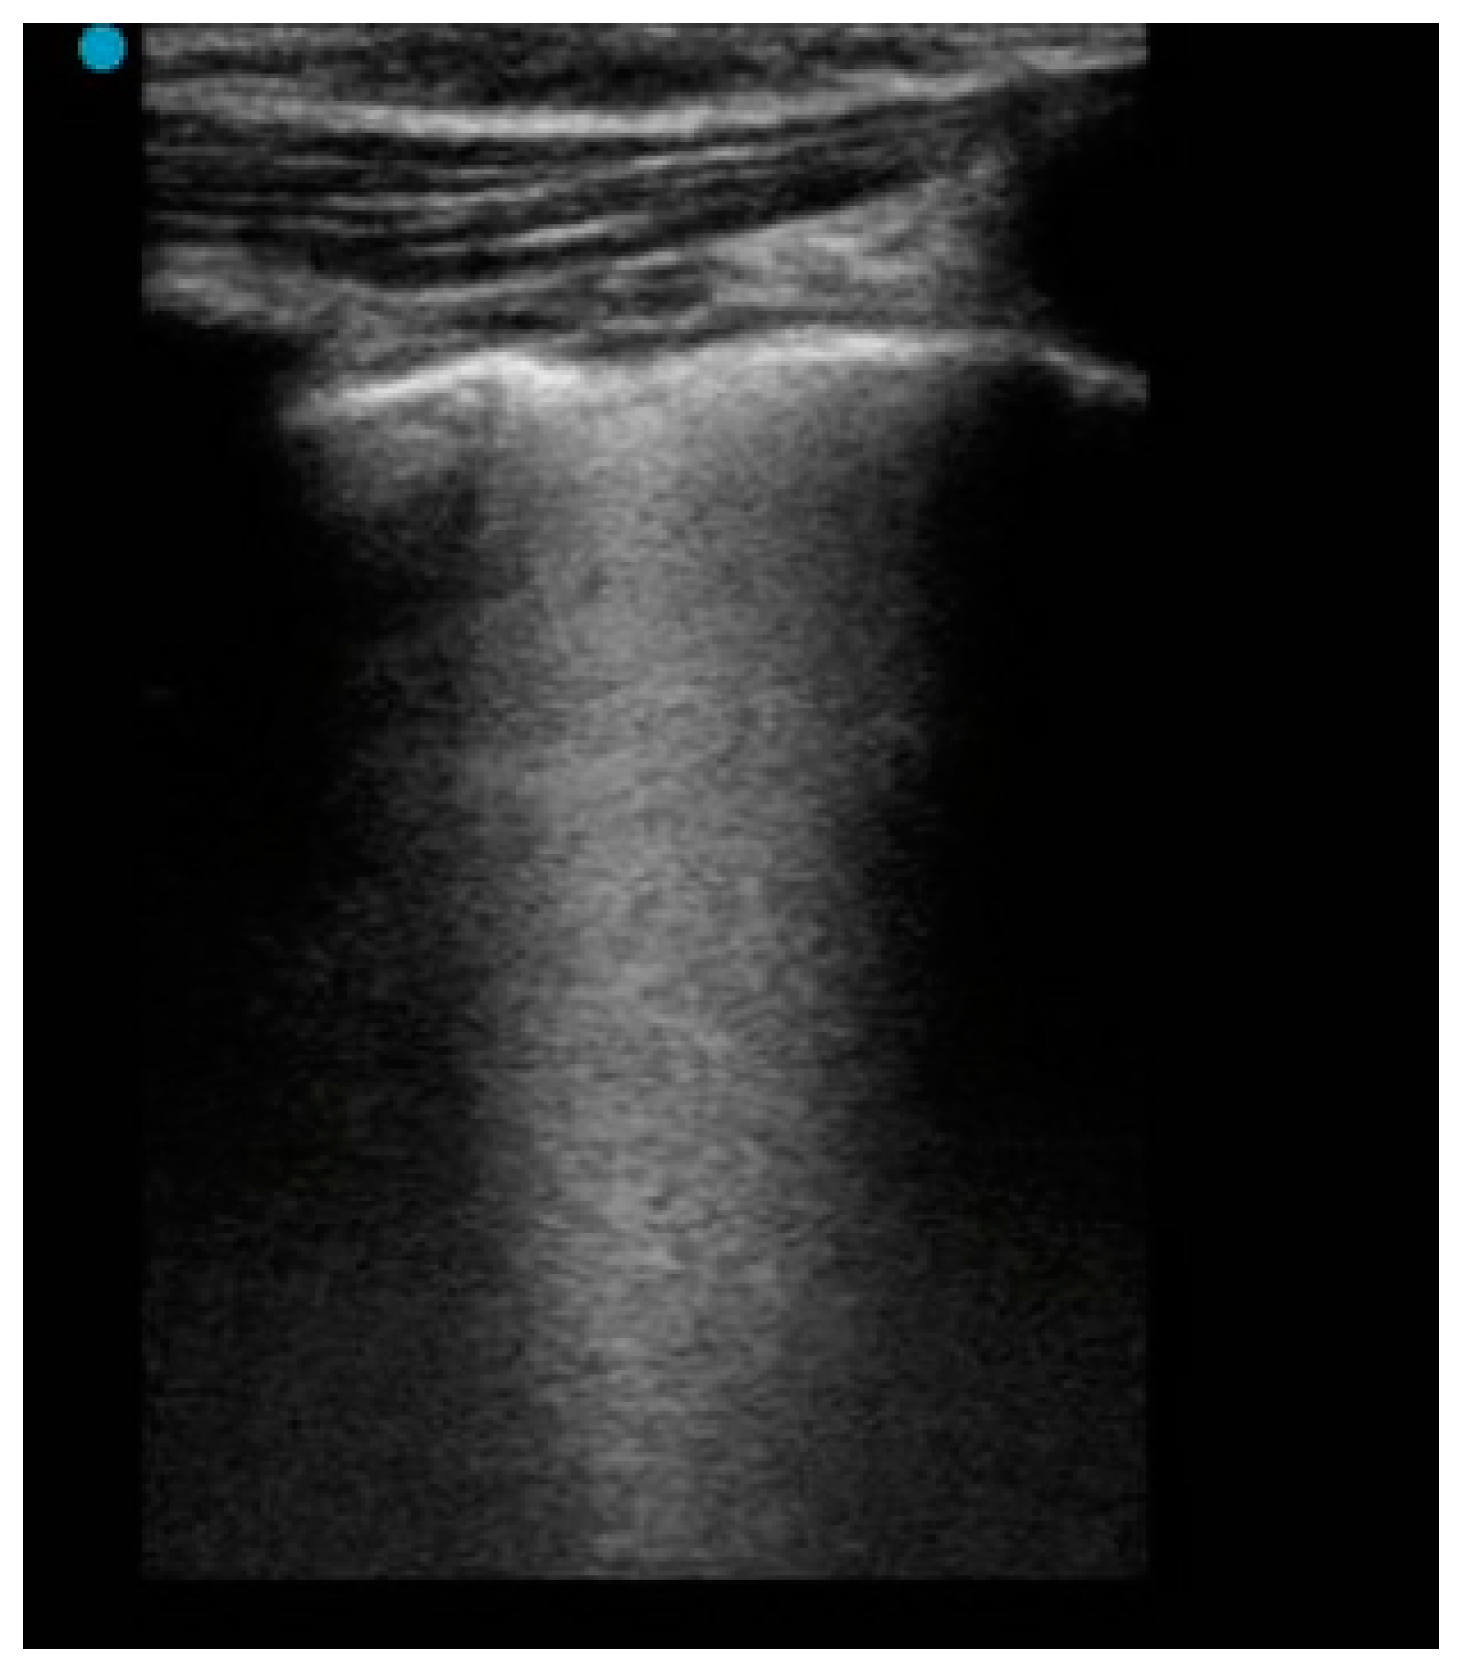

| B-Lines, n (%) | 15 (60.00) | 25 (89.29) | 0.003 |

| Several, non-coalescent B-Lines, n (%) | 3 (10.71) | 13 (46.43) | 0.003 |

| Sub-pleural consolidation, n (%) | 2 (7.14) | 8 (28.57) | 0.04 |

| Irregular pleural line, n (%) | 17 (60.71) | 24 (85.71) | 0.035 |